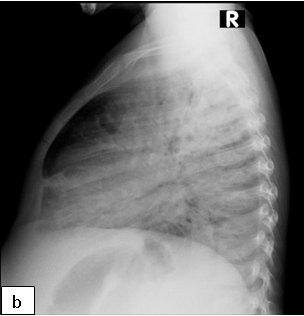

Diagnosis: CXR usually shows focal abnormalities with bronchial dilatation as shown in the figure below. TB may have a similar radiological picture to bronchiectasis and in a high TB burden area where there is over-reliance on radiological diagnosis for PTB, bronchiectasis may be missed or frequent retreatments of TB may occur. Almost a quarter of a cohort of children with HIV-related bronchiectasis in one study received two courses of antituberculosis treatment. In a high TB burden area, the differential diagnosis of an abnormal chest X-ray in children with chronic cough or previously treated TB should include bronchiectasis.

Where available a High-resolution computed tomography (HRCT) scanning is the standard test for diagnosis especially in the absence of characteristic chest radiograph findings of dilated airway, with thickened airway walls. Key features on CT scan: Enlarged internal bronchial diameter with bronchi that appear larger than the accompanying artery. Other findings include the failure of the larger airways to taper while progressing to the lung periphery, air fluid levels in the dilated airways, and the identification of airways in the extreme lung periphery. Other testing may be indicated to diagnose underlying conditions.